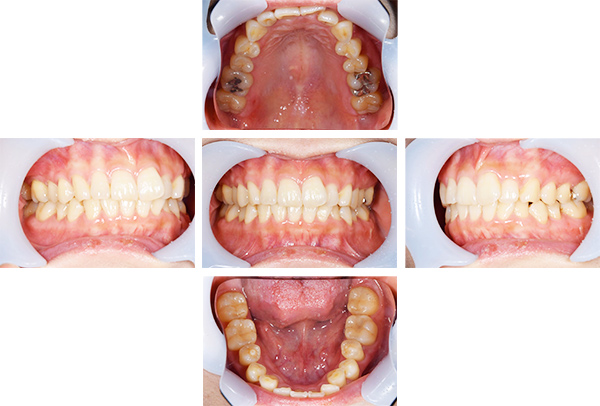

インレー・クラウン症例

治療前

治療後

治療期間 4回(3ヶ月)

費用 ・セラミックインレー11本

・ジルコニアクラウン1本

合計:660,000円

治療リスク・副作用 ・詰め物、被せ物をする時は自分の歯を削ることになります

・歯ぎしり・食いしばりが強い方は、セラミックが割れてしまうことがあります。